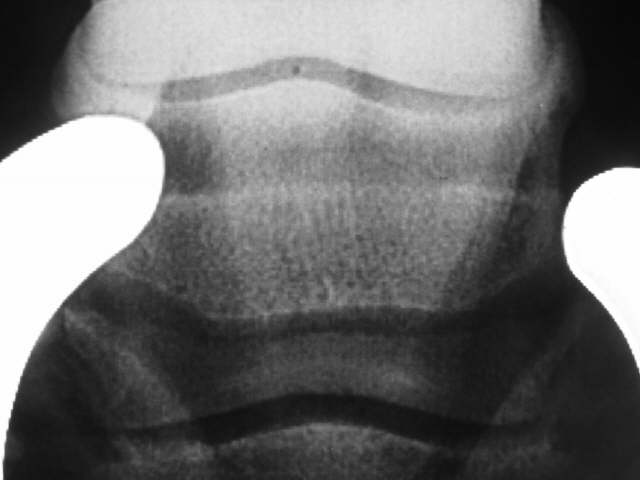

Strahlbein ohne sichtbare Gefäßkanäle. Das Strahlbein ist zum Teil durch das Hufeisen verdeckt. Die Knochendichte erscheint aufgelockert und grobmaschig, was aber Röntgentechnik bedingt ist.